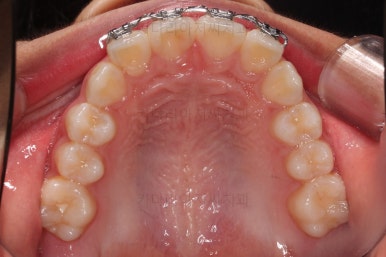

부산소아교정 초진 시 입안의 모습입니다.

윗니가 아랫니보다 많이 앞에 나와있고요.

심지어는 틈새가 벌어지기까지 했습니다.

윗니가 배열 되어있는 U자 형태(그릇 형태)가 아랫니보다 좁은 양상이고요.

이런 앵글씨 2급 부정교합에서는 아랫니가 윗니와 만나기 위해 솟구쳐서 과개교합(아래 앞니가 윗니 뒤쪽으로 깊숙히 올라가 있는 상태)이 나타나기까지 합니다.